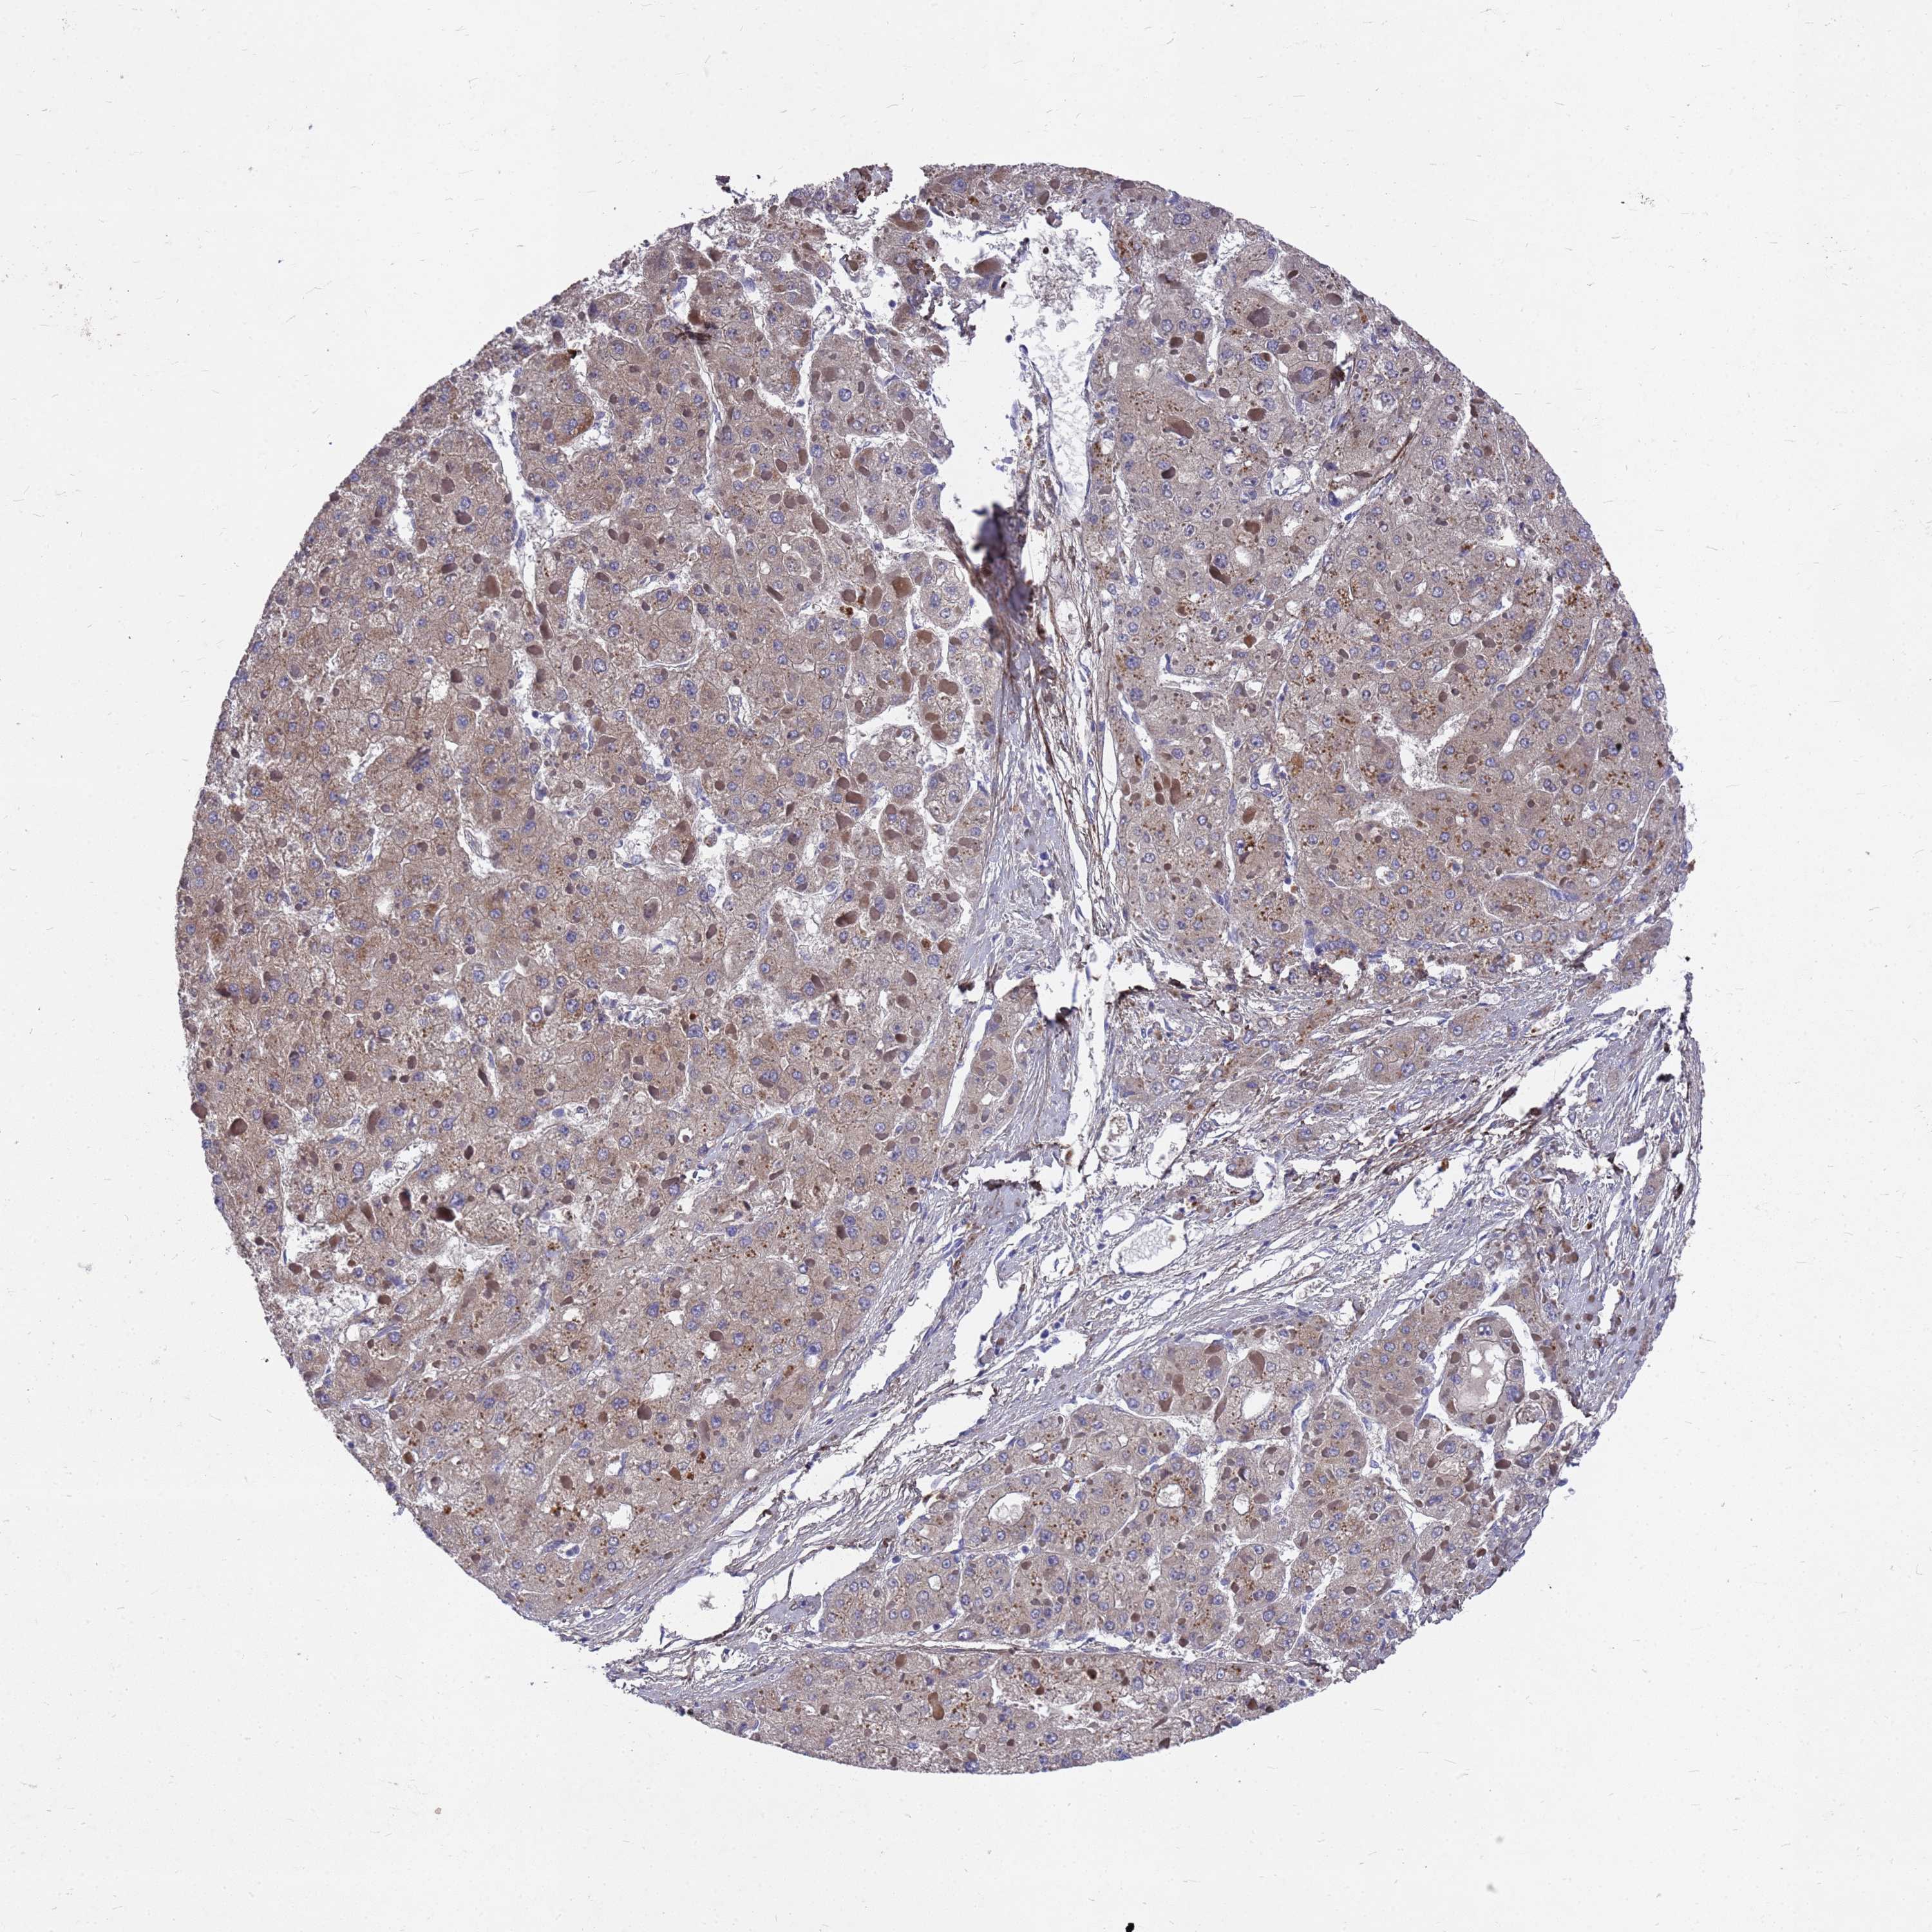

LIVER CANCER - Protein expressioni

A mouse-over function shows sample information and annotation data. Click on an image to view it in a full screen mode. Samples can be filtered based on level of antibody staining by selecting one or several of the following categories: high, medium, low and not detected. The assay and annotation is described here.

Note that samples used for immunohistochemistry by the Human Protein Atlas do not correspond to samples in the TCGA dataset.

Antibody stainingi

Antibody staining in the annotated cell types in the current human tissue is reported as not detected, low, medium, or high, based on conventional immunohistochemistry profiling in selected tissues. This score is based on the combination of the staining intensity and fraction of stained cells.

Each image is clickable and will lead to virtual microscopy that enables deeper exploration of all samples and also displays staining intensity scores, fraction scores and subcellular localization as well as patient and tissue information for each sample.

Antibody HPA044549

Staining

High

Medium

Low

Not detected

Intensity

Strong

Moderate

Weak

Negative

Quantity

>75%

75%-25%

<25%

None

Location

Nuclear

Cytoplasmic/membranous

Cytoplasmic/membranous,nuclear

Cholangiocarcinoma

Carcinoma, Hepatocellular, NOS